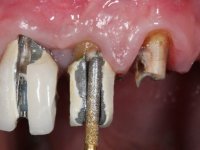

•    Metal-ceramic fixed partial denture (FPD) (11-15) supported by three dental implants in 11, 13 and 15.

•    Small exposure of the implant neck in 11 position.

Ten weeks after the surgery the screw-retained implant bridge was removed, and an impression was done with an open-tray procedure. The inter-maxilary relations were recorded and the models were mounted in a semi-adjustable articulator. This point was considered the “initial situation” of the prosthodontic rehabilitation.

Then, a double-mixture technique was used in the impression of the 1st, 2nd and 3rd quadrants. Gingival retraction was done with only one cord.

After it, the dental technician constructed the ceramic overlays to rehabilitate 47-44, that were bonded while testing the CAD-CAM zirconia frameworks in the maxilla. In this session, the provisional FPDs in the 1st and 2nd quadrant were removed separately to allow a bite-registration with the inter-maxillary relations that the patient supported with the provisional restorations, and colour was evaluated and registered.